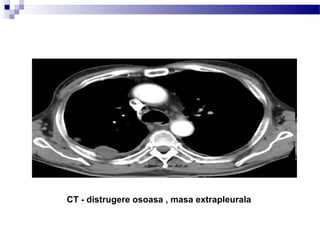

– acest lucru poate fi un indicator foarte important în stabilirea etiologiei leziunii;

astfel, o masă care este aproape de peretele toracic i care implică distruc iaș ț

osoasă a unei coaste, are probabilitate ridicată de malignitate (de i, nici acestș

lucru nu este un indicator absolut al malignita ii, deoarece unele leziuniț

pulmonare infec ioase, cum ar fi actinomicoza, pot distruge coastele adiacente).ț

LOCALIZAREA MASEI

Intraparenchimatosa vs. pleurala vs. extrapleurala

A = intraparenchimatos

B = pleural

C = extrapleural

CT - masa, cel mai probabil pleurala (sageata rosie); revarsat pleural posterior

CT - distrugere osoasa , masa extrapleurala